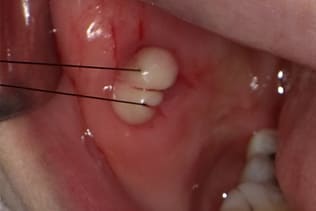

症例6 頬粘膜腫瘍(線維腫)の手術(40歳代 女性)

右側の頬にできものができ治らないので当クリニックを受診された。

右側頬粘膜に境界明瞭な弾性硬の腫瘍を認め、線維腫を疑い腫瘍摘出術を施行した。

局所浸潤麻酔を行い、腫瘍に糸をかけ、十分にカウンタートラクションをかけた状態で、腫瘍の境界に沿ってメスで上皮を木の葉状に切開し、牽引しながらメスで周囲の結合組織と腫瘍の境界を鋭利に剥離する。切る感じではなくて削ぐ感じでメスを用いることが重要である。